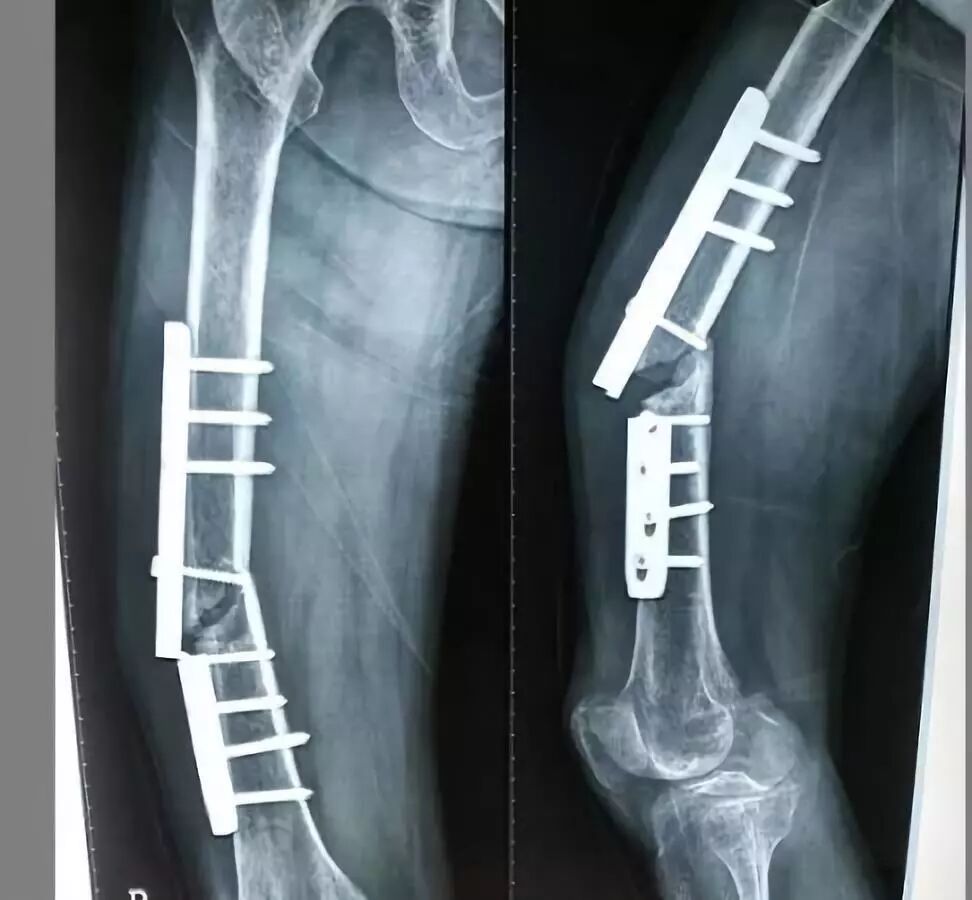

(图为患者术前术后DR片)

该技术骨折处不切开,创伤小、切口小、术中出血少,基本上没有并发症,病人术后第二天即可拄拐下床行走,骨折恢复快。